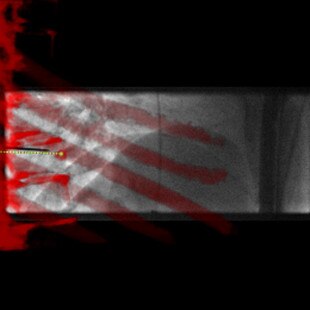

INTERVENTIONS AU NIVEAU DU RACHIS

Guider